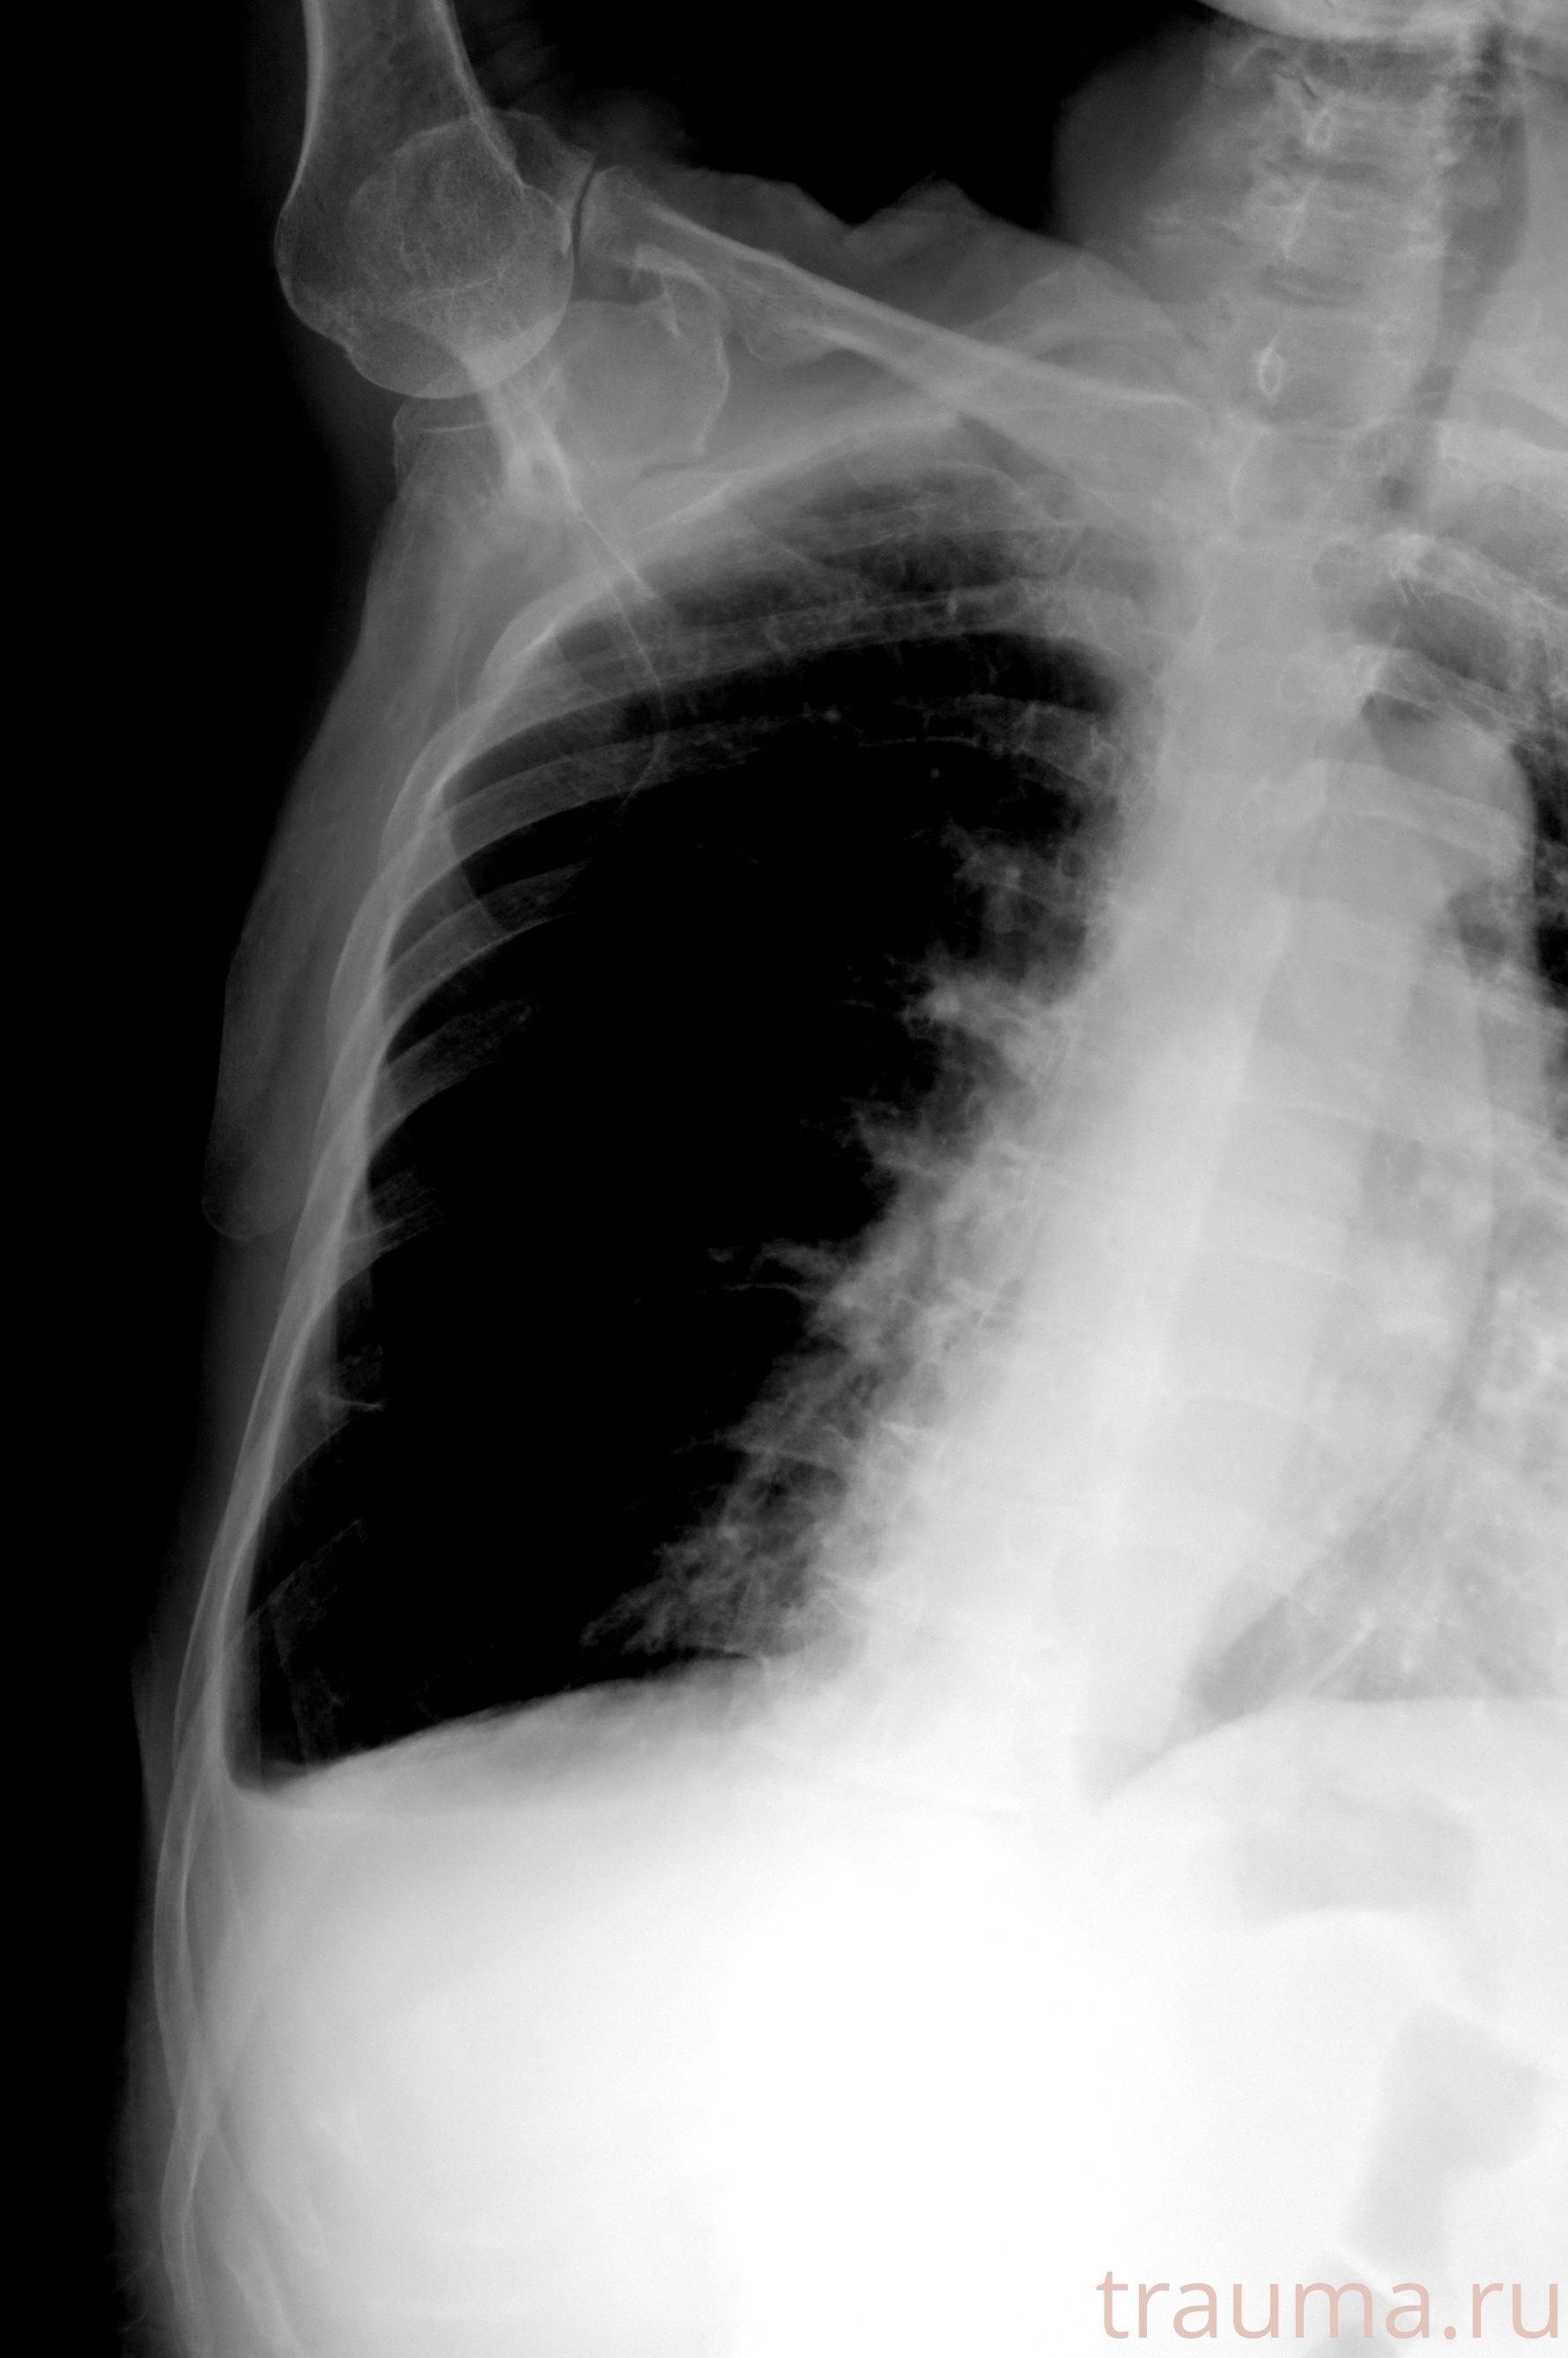

Рентгенограммы

Натуживание 26.12.2025 21:16:34

Рентген на дому: по вашему адресу приезжает врач-рентгенолог, травматолог-ортопед с мобильным рентгеновским аппаратом, проводит диагностику травмы или заболевания, делает необходимые рентгенограммы, дает рекомендации по дальнейшему лечению. Получить качественные снимки в домашних условиях возможно благодаря уникальной методике, разработанной МосРентген Центром для института  Склифосовского